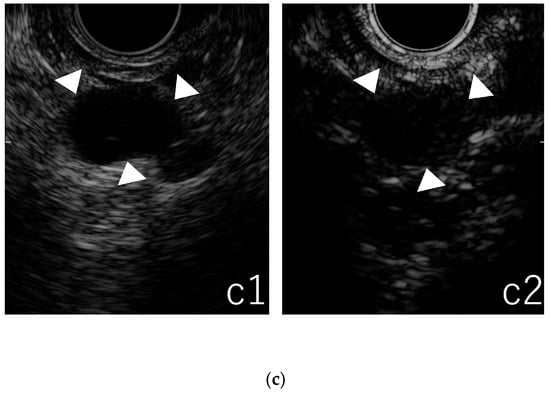

3.3. Qualitative Evaluation in CE-EUS

3.4. Quantitative Evaluation in TIC